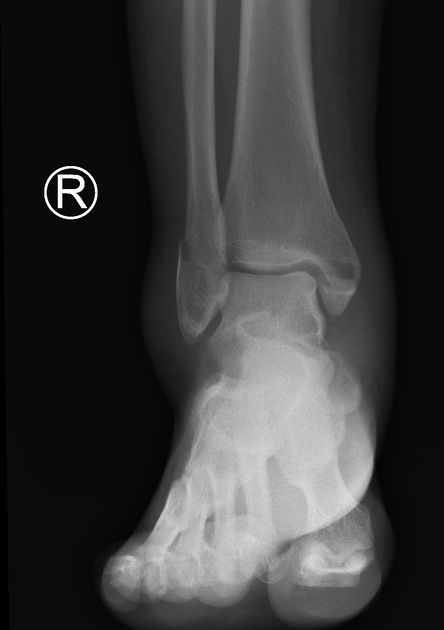

Explain the trimalleolar fracture

fracture of the ankle that involves the medial malleoli, lateral malleoli, and the distal posterior tibia

Explain the Potts fracture

bimalleolar fracture of the medial and lateral malleoli

What kind of fracture is shown?

Jones

What kind of fracture is shown?

dancers

What kind of fracture is shown?

trimalleolar

What kind of fracture is shown?

bimalleolar